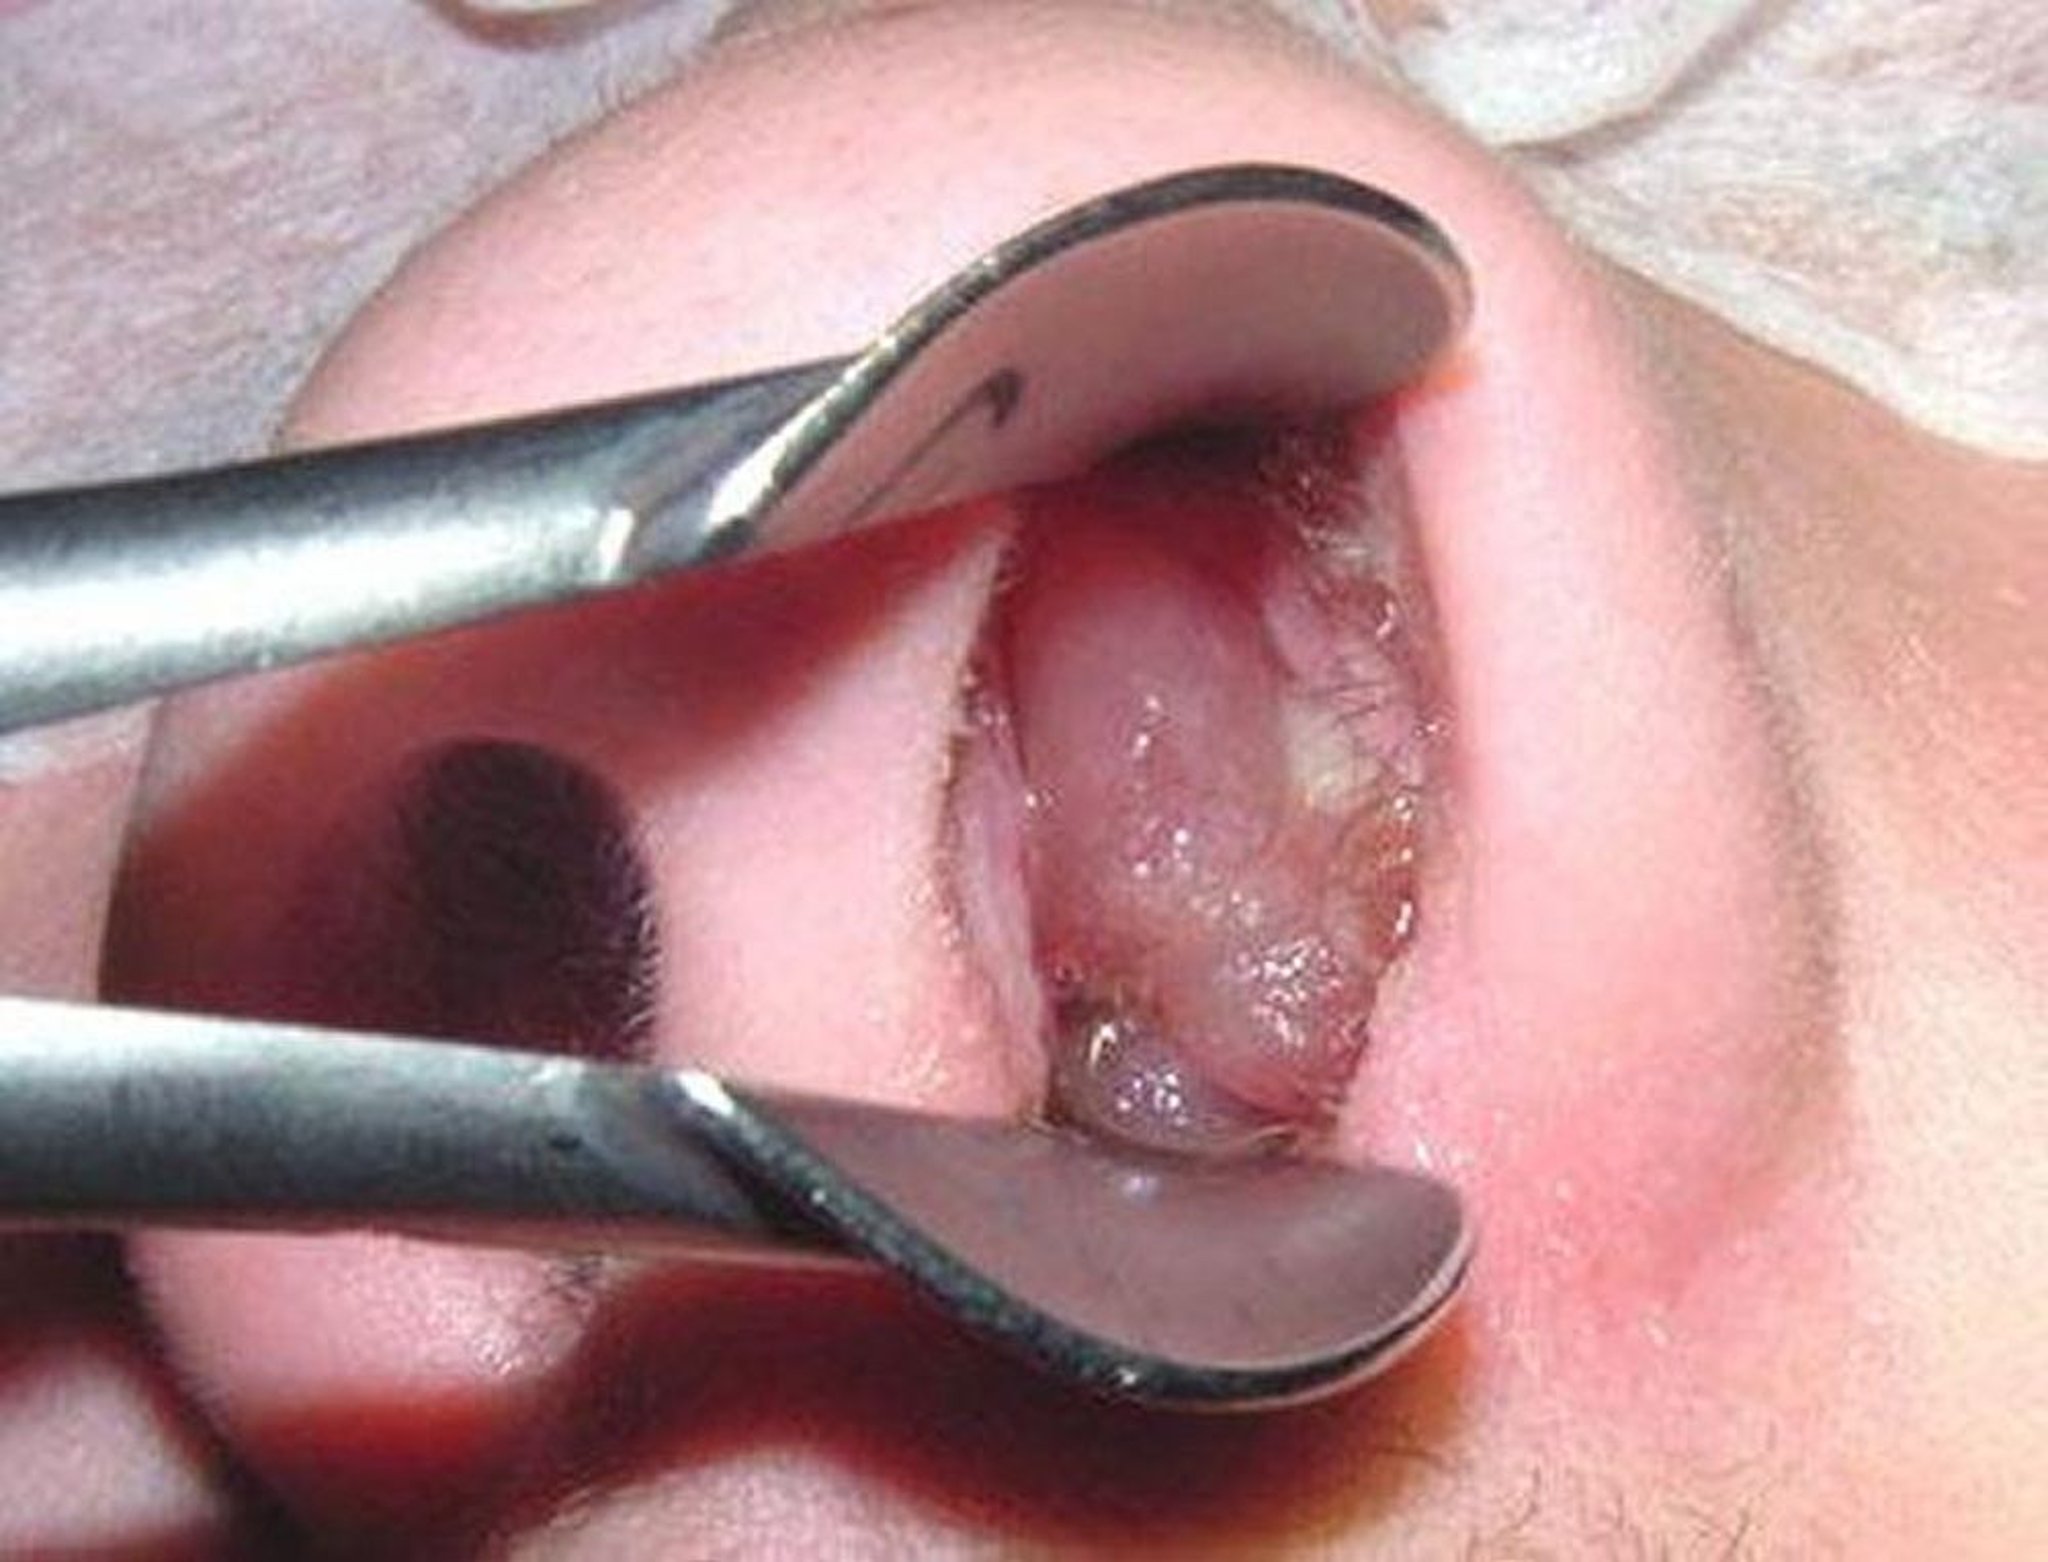

Un polipo nasale maturo può assomigliare a un chicco d’uva senza buccia e semi.

Immagine fornita dal Dott. Bechara Ghorayeb.